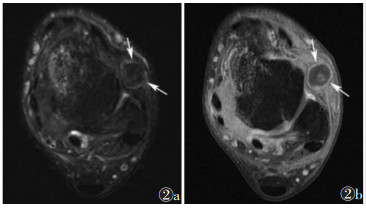

2 前外踝撞击综合征(anterolateral ankle impingement syndrome)前外踝撞击综合征多继发于踝关节内翻引起的外侧副韧带损伤及前外侧沟内软组织异常肥厚(图 2)。

| 注:图 2a为轴位脂肪抑制T2WI图像,显示前外侧隐窝中1个边界清楚、圆形、低至中等信号强度病变(箭头),撞击前距腓韧带,距骨内侧穹窿可见骨髓水肿;图 2b为轴位脂肪抑制T1WI增强扫描图像,显示纤维化瘢痕组织的外围边缘增强(箭头) 图 2 [1] 前外踝撞击综合征MRI图像 |